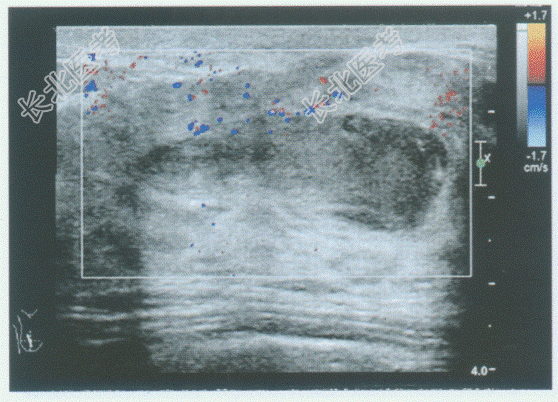

- 单项选择题临床资料:女, 29岁,哺乳期, 自述右乳房肿痛1周。

临床物理检查:右乳房红、肿、热、痛, 体温38.5℃。

超声综合描述:右乳头后方可见低回声区, 形态不规则,边界显示不清, 内可见不规则无回声区,无回声区内可见中强回声光点浮动, 探头加压局部疼痛明显,CDFI: 周边可见散在点状动静脉血流信号。见下图及彩图。

超声提示: A、急性乳腺炎合并乳腺脓肿